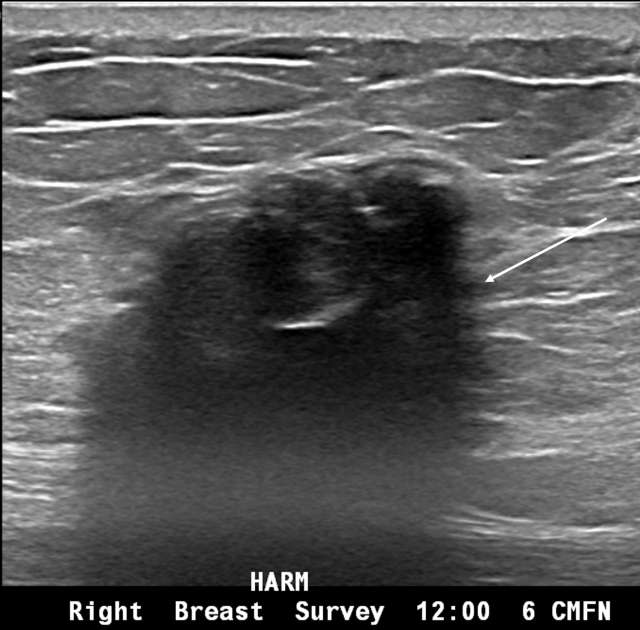

When calcifications are visualized on US, they typically appear as hyperechoic foci, which may or may not cause shadowing. Doppler US can also be used to detect calcifications, which may demonstrate “twinkling” artifact. Calcifications may be seen within a mass, outside a mass, or within ducts2. When suspicious mammographic calcifications are also visualized on ultrasound, they tend to have a larger number of calcifications and involve a larger area on mammography. In these cases, the calcifications are also most frequently seen associated with a mass on ultrasound, despite there being no mass visualized mammographically1.

Within a mass, calcifications may appear as hyperechoic foci, typically without posterior acoustic shadowing unless they are larger or coarse.